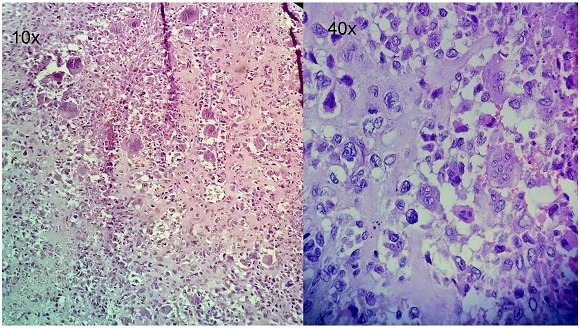

Figure 3 H&E Stained section show osteoclast like giant cells , mononuclear malignant cells and malignant osteoid (Giant cell rich Osteosarcoma).